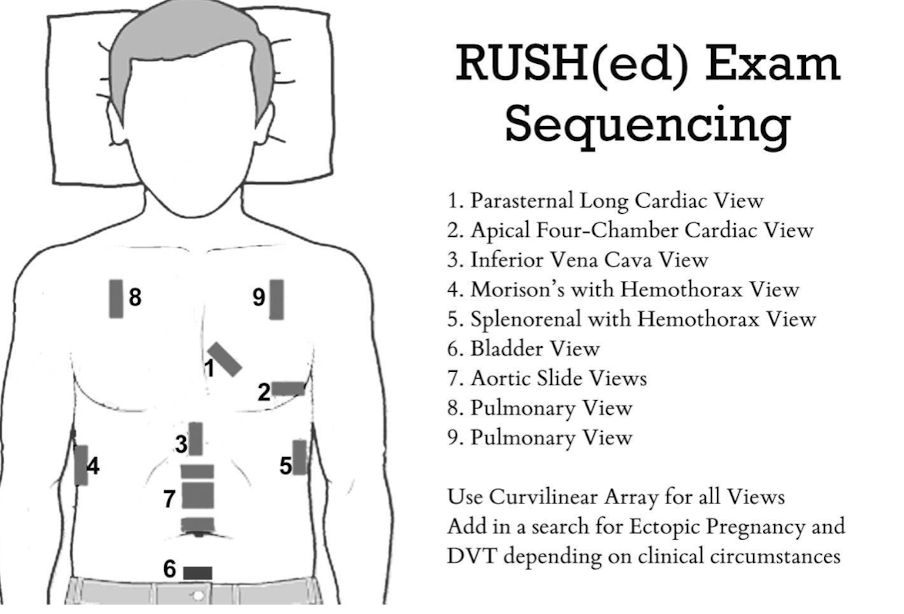

E-FAST (Extended Focused Assessment with Sonography in Trauma)

bedside ultrasound protocol design to detect peritoneal fluid, pericardial fluid, pneumothorax and/or hemothorax in trauma patient

RUSH Exam

ultrasound to quickly assess any patient with undifferentiated shock and hypertension

What imaging is used to visualize the gallbladder, appendix, complete abdomen, kidneys and lungs for pneumothorax (eFAST/RUSH), skin and soft tissue?